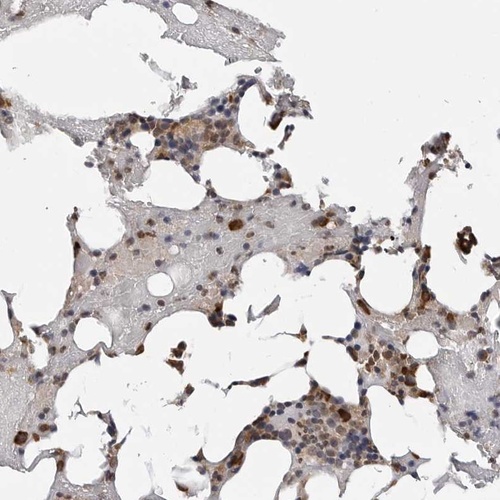

Immunohistochemical staining of human bone marrow shows strong cytoplasmic and nuclear positivity in bone marrow poietic cells.